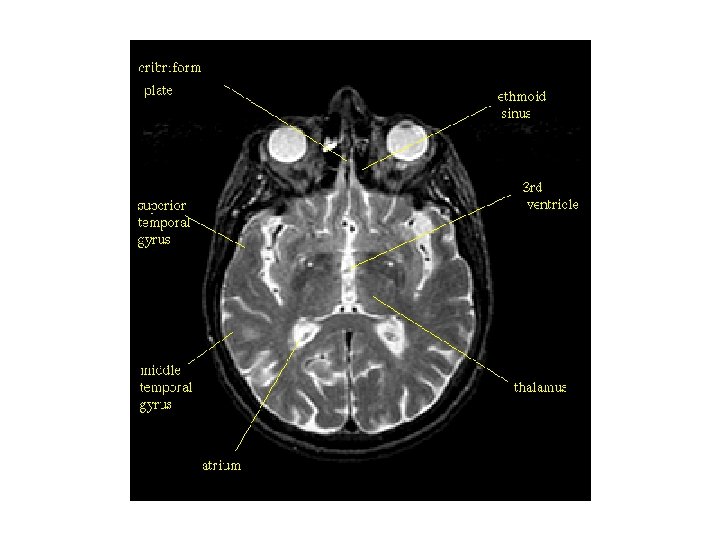

뇌실계(ventricular system)의 구조 1. 전두각(frontal horn, 전각 anterior horn) 3. 측면삼각(collateral trigone, 외측뇌실방 atrium) 5. 측두각(temporal horn, 하각 inferior horn) 2. 중심부분(central portion, body) 7. 제 3뇌실(3 rd ventricle) 4. 후두각(occipital horn, 후각 posterior horn) 6. 몬로공(formanen of Monro, 뇌실간공 intervertebral foramen) 8. 중뇌수도관(cerebral aqueduct, 대뇌수도) 9. 제 4뇌실(4 th ventricle) 10. 시상간접합부(interthalamic adhesion, 시상간교) 11. 시각상오목(supraoptic recess, 시삭상와) 13. 송과선상오목(suprapineal recess, 송과상 와) 15. 외측오목(lateral recess, 외측와) 12. 깔때기오목(infundibular recess, 누두와) 14. 송과선오목(pineal recess, 송과체와)